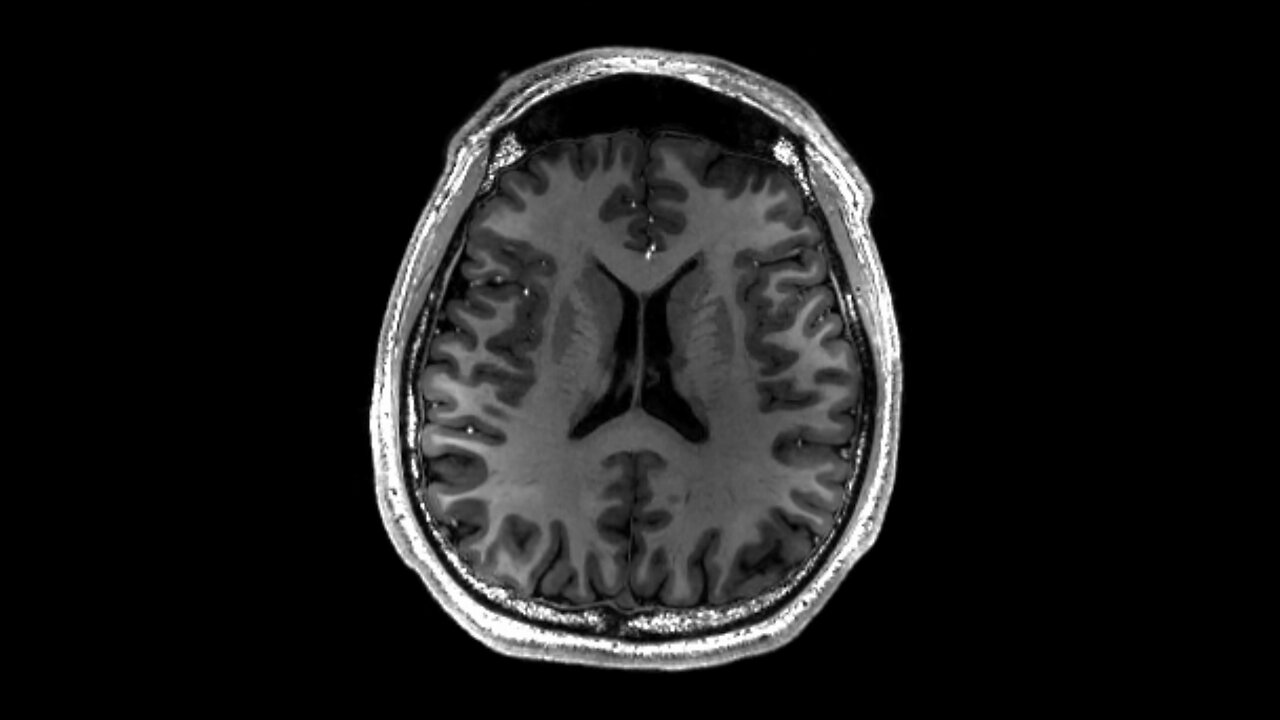

The brain DOES NOT mature at 25, but rather around a decade earlier, near the end of puberty. Most people are either finished or nearly finished with puberty by ages 15-16 years and to say that the brain takes a decade longer is ridiculous.

- The brain hits adult size by age 15

- At the same age, the brain also peaks in key functions such as memory and intelligence

- Puberty is also incidentally finished or nearly finished by age 15 in most people (males who start puberty later than average can grow into their late teens or even early 20s but in general, by age 15, puberty is either finished or nearly finished)